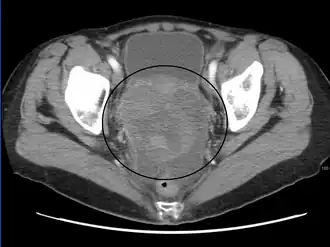

Diagnosis

Examination

Diagnosis of ovarian cancer starts with a physical examination (including a pelvic examination), a blood test (for CA-125 and sometimes other markers), and transvaginal ultrasound.[26][58] Sometimes a rectovaginal examination is used to help plan a surgery.[29] The diagnosis must be confirmed with surgery to inspect the abdominal cavity, take biopsies (tissue samples for microscopic analysis), and look for cancer cells in the abdominal fluid. This helps to determine if an ovarian mass is benign or malignant.[26]

Ovarian cancer's early stages (I/II) are difficult to diagnose because most symptoms are nonspecific and thus of little use in diagnosis; as a result, it is rarely diagnosed until it spreads and advances to later stages (III/IV).[59] Additionally, symptoms of ovarian cancer may appear similar to irritable bowel syndrome. In women in whom pregnancy is a possibility, BHCG level can be measured during the diagnosis process. Serum alpha-fetoprotein, neuron-specific enolase, and lactate dehydrogenase can be measured in young girls and adolescents with suspected ovarian tumors as younger women with ovarian cancer are more likely to have malignant germ cell tumors.[26][31]

A physical examination, including a pelvic examination, and a pelvic ultrasound (transvaginal or otherwise) are both essential for diagnosis: physical examination may reveal increased abdominal girth and/or ascites (fluid within the abdominal cavity), while pelvic examination may reveal an ovarian or abdominal mass.[28] An adnexal mass is a significant finding that often indicates ovarian cancer, especially if it is fixed, nodular, irregular, solid, and/or bilateral. 13–21% of adnexal masses are caused by malignancy; however, there are other benign causes of adnexal masses, including ovarian follicular cyst, leiomyoma, endometriosis, ectopic pregnancy, hydrosalpinx, tuboovarian abscess, ovarian torsion, dermoid cyst, cystadenoma (serous or mucinous), diverticular or appendiceal abscess, nerve sheath tumor, pelvic kidney, ureteral or bladder diverticulum, benign cystic mesothelioma of the peritoneum, peritoneal tuberculosis, or paraovarian cyst. Ovaries that can be felt are also a sign of ovarian cancer in postmenopausal women. Other parts of a physical examination for suspected ovarian cancer can include a breast examination and a digital rectal exam. Palpation of the supraclavicular, axillary, and inguinal lymph nodes may reveal lymphadenopathy, which can be indicative of metastasis. Another indicator may be the presence of a pleural effusion, which can be noted on auscultation.[31]

CT scanning is preferred to assess the extent of the tumor in the abdominopelvic cavity, though magnetic resonance imaging can also be used.[28] CT scanning can also be useful for finding omental caking or differentiating fluid from solid tumor in the abdomen, especially in low malignant potential tumors. However, it may not detect smaller tumors. Sometimes, a chest x-ray is used to detect metastases in the chest or pleural effusion. Another test for metastatic disease, though it is infrequently used, is a barium enema, which can show if the rectosigmoid colon is involved in the disease. Positron emission tomography, bone scans, and paracentesis are of limited use; in fact, paracentesis can cause metastases to form at the needle insertion site and may not provide useful results.[29] However, paracentesis can be used in cases where there is no pelvic mass and ascites is still present.[29] A physician suspecting ovarian cancer may also perform mammography or an endometrial biopsy (in the case of abnormal bleeding) to assess the possibility of breast malignancies and endometrial malignancy, respectively. Vaginal ultrasonography is often the first-line imaging study performed when an adnexal mass is found. Several characteristics of an adnexal mass indicate ovarian malignancy; they usually are solid, irregular, multilocular, and/or large; and they typically have papillary features, central vessels, and/or irregular internal septations.[31] However, SCST has no definitive characteristics on radiographic study.[32]